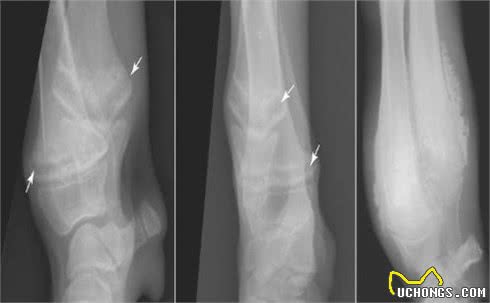

5个月大的肥大性骨营养不良大丹犬尺骨X光片

X光线通常显示病变骨头的变化,例如与生长板平行线的外观,骨密度的变化以及生长板周围的钙化。